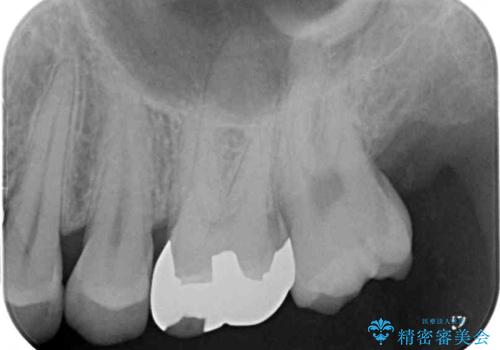

- 奥歯の詰め物が外れてしまったとのことで来院された患者様です。

幾度も詰め物治療を行ったため継ぎ接ぎだらけとなっていたため、インレーにて修復治療をすることとしました。

咬合力が強いため、ゴールド合金(PGA)のインレーを選択することとしました。

ゴールドインレーは銀歯のインレーやセラミックインレーと比べ、「技工操作の精度が高く、適合が著しく良い」というメリットがあります。特に上の奥歯は歯科医師の操作が行いにくいため、「適合の良さ」は再治療のリスクを防ぐ上でとても重要な要素となります。

上の奥歯は金属色が見えることもないため、審美的な問題は全くありません。